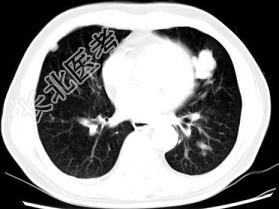

- 单项选择题男,64岁, 咳嗽半月,咯血1天, 不发热,结合图像, 最可能的诊断是 ( )

A、金葡菌肺炎

B、肺转移瘤

C、肺结核

D、结节病

E、组织胞浆菌病